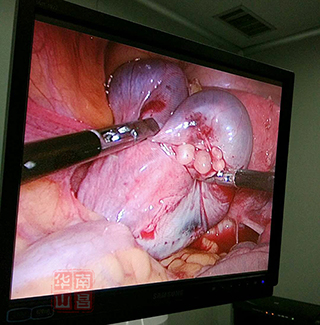

左侧输卵管积水